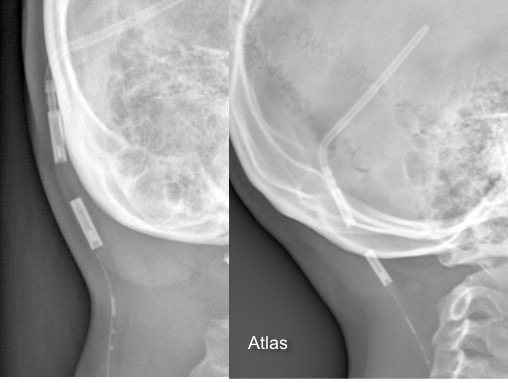

il existe un grand nombre de valves ; il n’est pas toujours aisé de les reconnaitre radiologiquement. voici la liste des plus courantes :

comment reconnaitre radiologiquement le type de valve ?